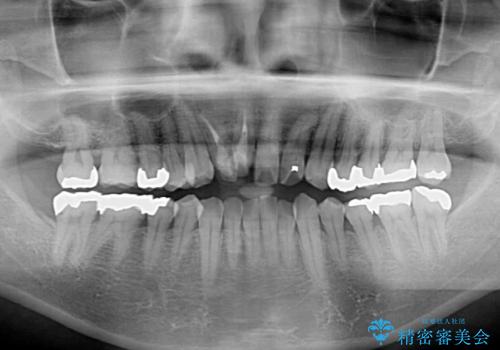

- 隠れるほどに内側に転位しいてる前歯を気にして来院された患者様です。

仕事柄海外出張が多いとのことで、インビザラインにて矯正治療を行うこととしました。

矯正治療後は、前歯や下顎の奥歯など、むし歯治療途中の歯をオールセラミッククラウンにて補綴治療を行うこととしました。

治療途中で海外に長期滞在することとなり、5年近く帰国することができなかったため、治療期間は非常に長いものとなりました。

内側に転位していた前歯は、矯正治療では治しきることができませんでしたが、幸いにもオールセラミッククラウンに置き換える予定であったため、希望通りの仕上がりとなりました。